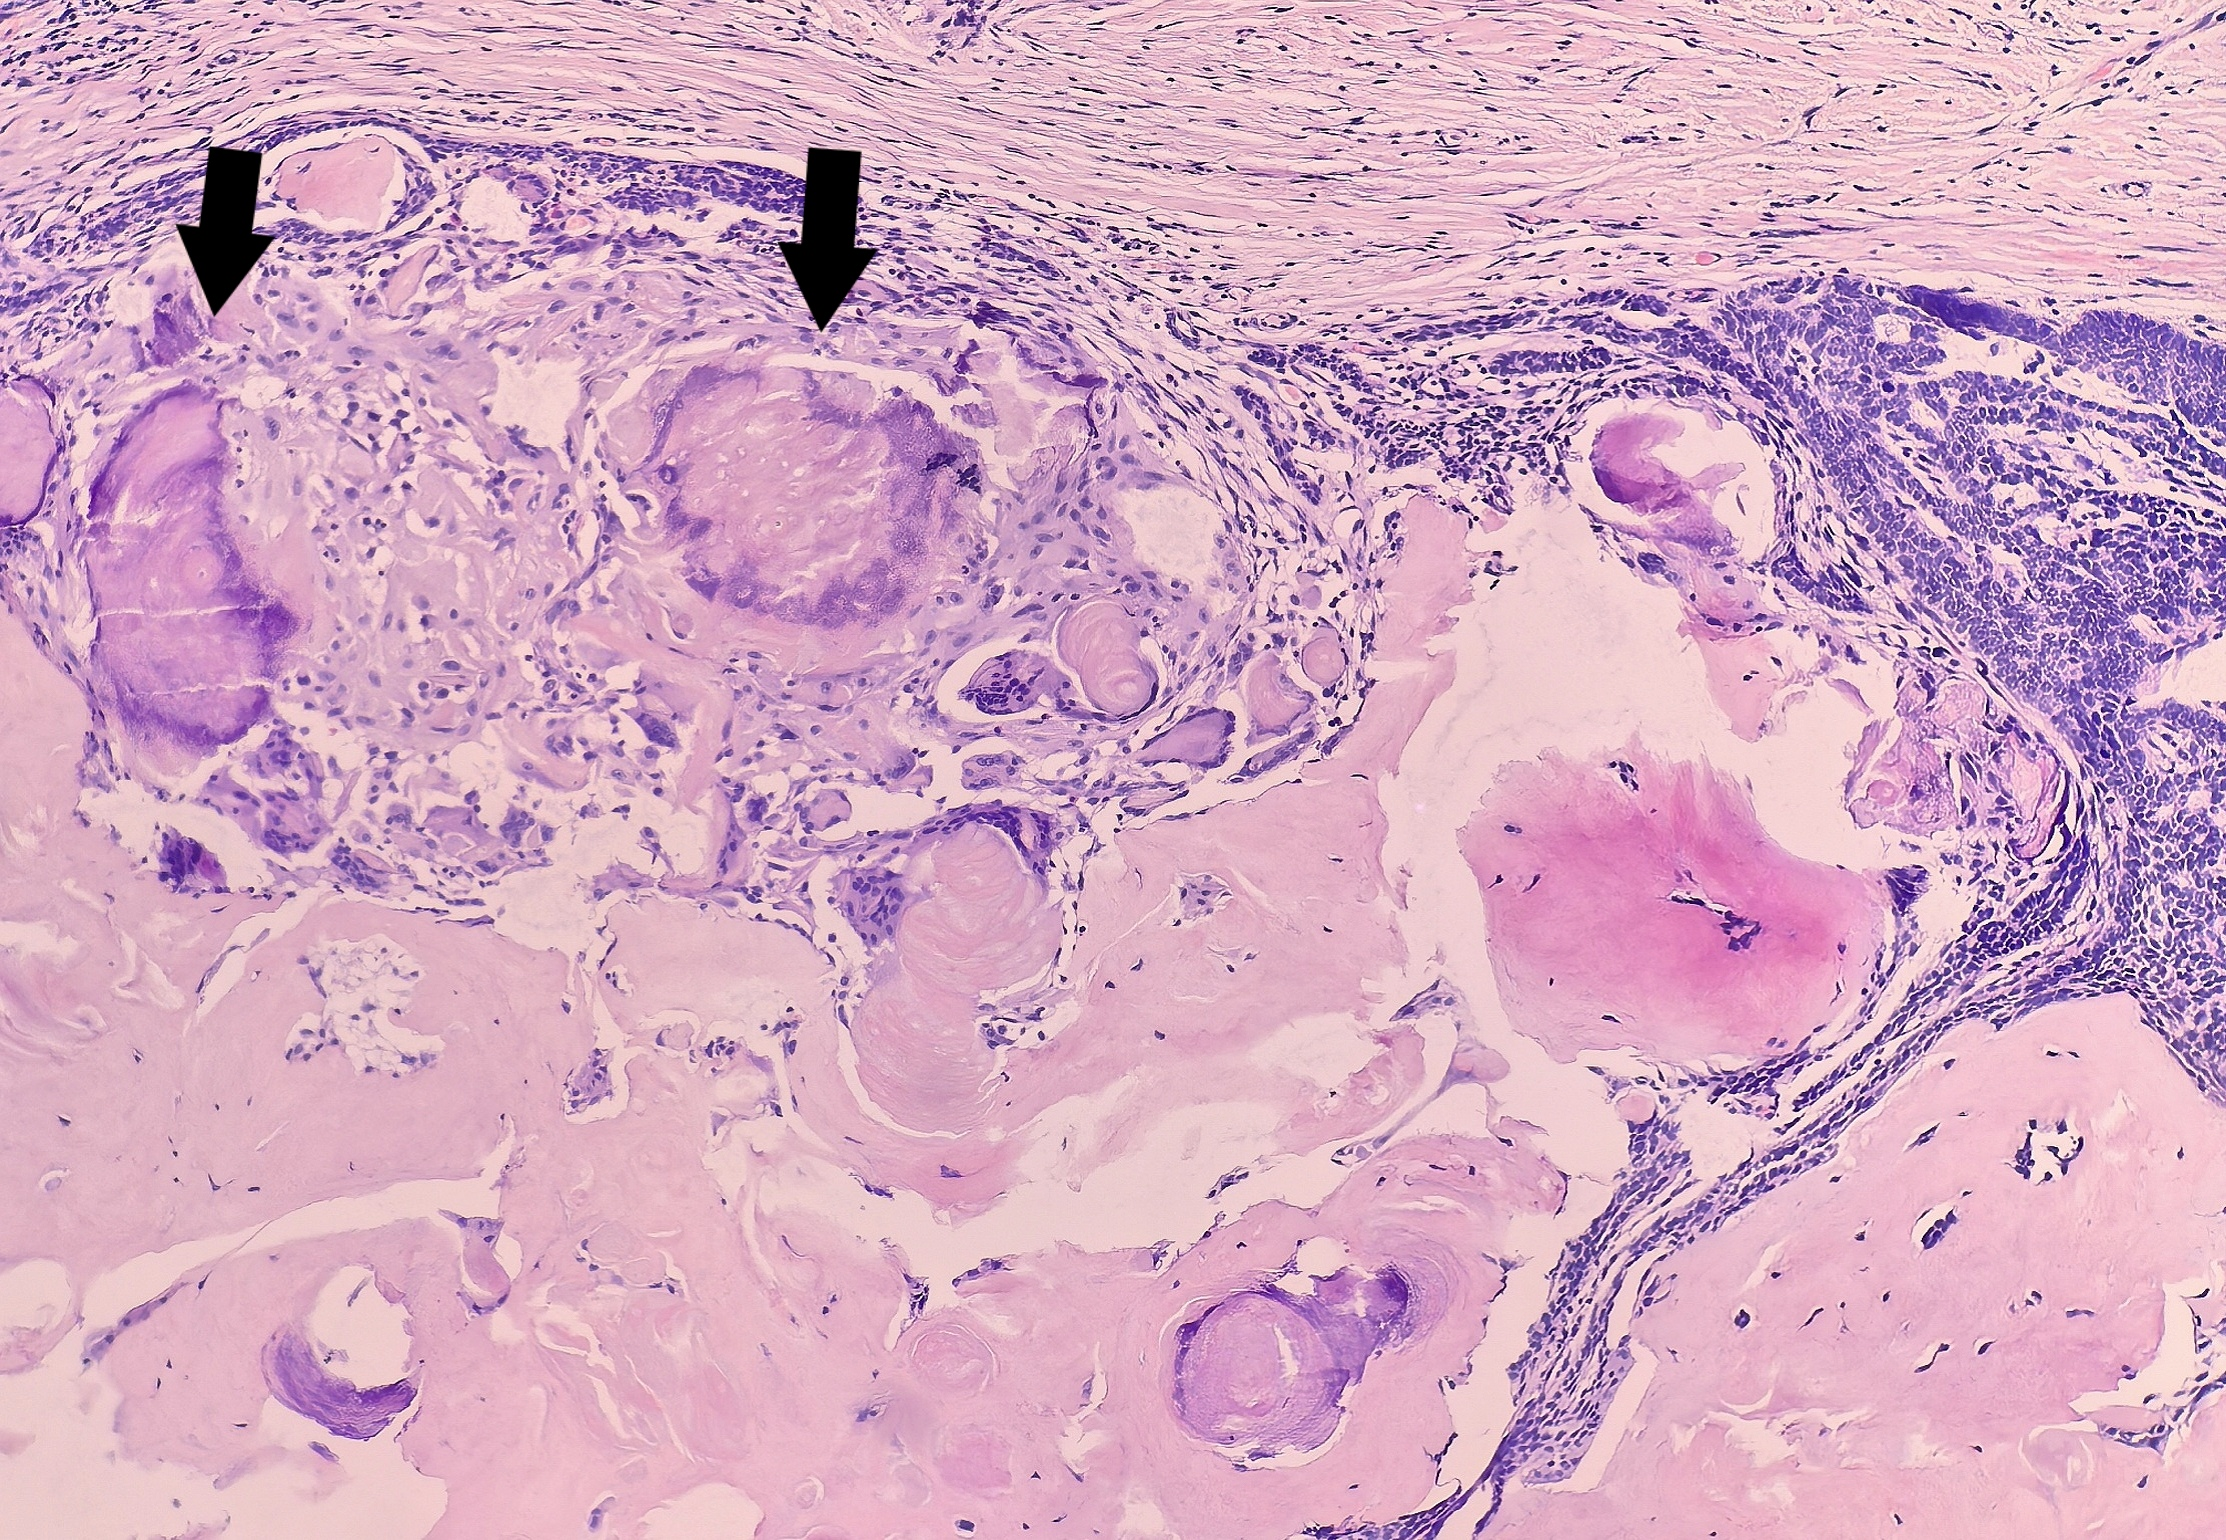

本病例最显著的特征是间质可见广泛的骨样基质,呈均质,粉染的不规则编织状存在,可见骨陷窝样结构(图8、9),与肿瘤上皮穿插交错存在。

部分区域可见钙化(图10)。